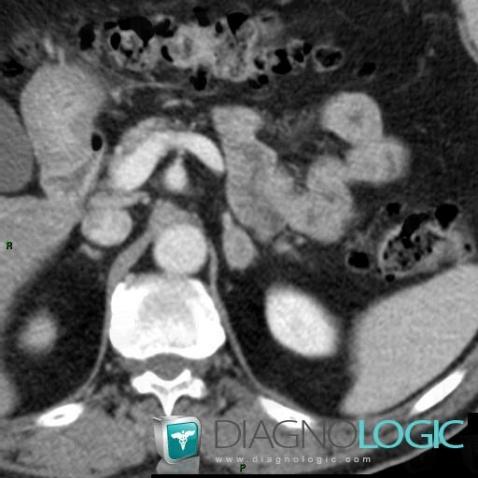

Adenoma, Adrenal glands, CT

Here is the specific information in the key image above:

- Diagnosis Adenoma, Location(s) Adrenal glands, with gamuts Unilateral adrenal mass